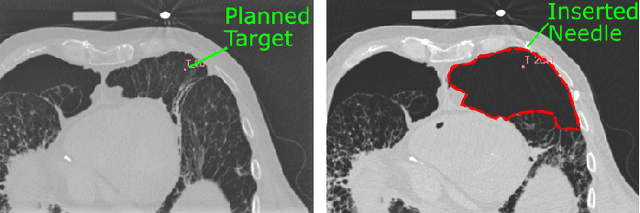

Abstract:In pathology and legal medicine, the histopathological and microbiological analysis of tissue samples from infected deceased is a valuable information for developing treatment strategies during a pandemic such as COVID-19. However, a conventional autopsy carries the risk of disease transmission and may be rejected by relatives. We propose minimally invasive biopsy with robot assistance under CT guidance to minimize the risk of disease transmission during tissue sampling and to improve accuracy. A flexible robotic system for biopsy sampling is presented, which is applied to human corpses placed inside protective body bags. An automatic planning and decision system estimates optimal insertion point. Heat maps projected onto the segmented skin visualize the distance and angle of insertions and estimate the minimum cost of a puncture while avoiding bone collisions. Further, we test multiple insertion paths concerning feasibility and collisions. A custom end effector is designed for inserting needles and extracting tissue samples under robotic guidance. Our robotic post-mortem biopsy (RPMB) system is evaluated in a study during the COVID-19 pandemic on 20 corpses and 10 tissue targets, 5 of them being infected with SARS-CoV-2. The mean planning time including robot path planning is (5.72+-1.67) s. Mean needle placement accuracy is (7.19+-4.22) mm.